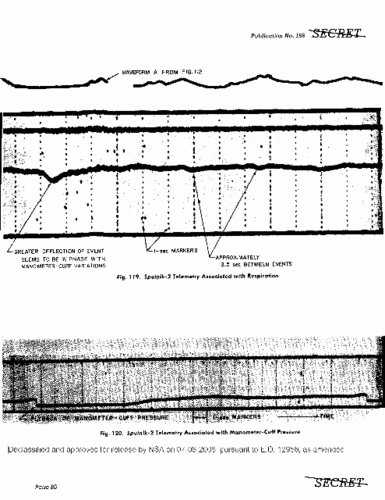

Данные биометрии во время полета на космическом корабле «Спутник-2» собаки Лайки, которые американцы сумели перехватить. Два графика, расшифрованные американскими специалистами — это пульс Лайки (вверху) и ее кровяное давление.